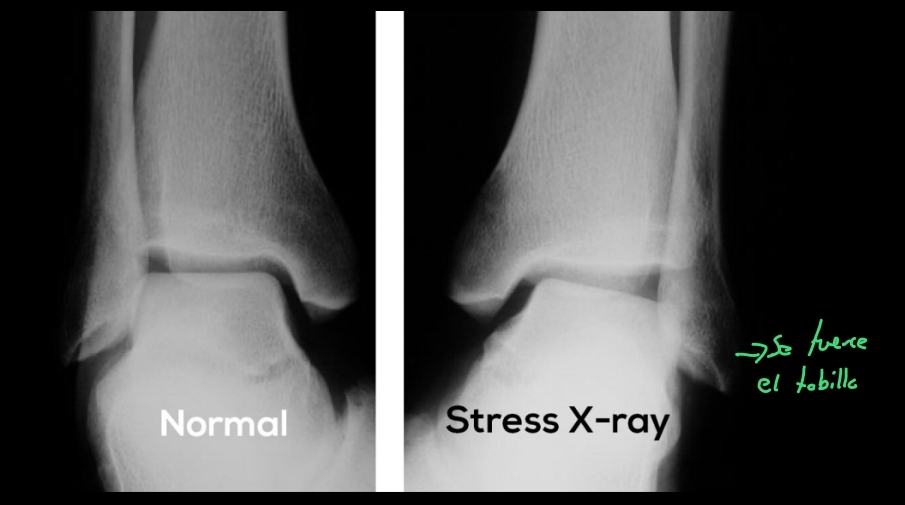

Qué se ve en una Rx en un esguince de tobillo

A

No se ven losligamentos, pero sí datos secundarios

- Edema

- Aumento del espacio entre peroné y astrágalo

- decarta fracturas